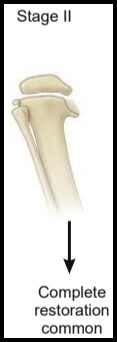

14

Q

Doença de Blount

Langenskiöld II (2) ?

A

3 - 4 anos

* Bico Medial

* Depressão Metafisária

15

Langenskiöld II - Marco em Relação ao TTO ?

Limite para ÓRTESE

KAFO